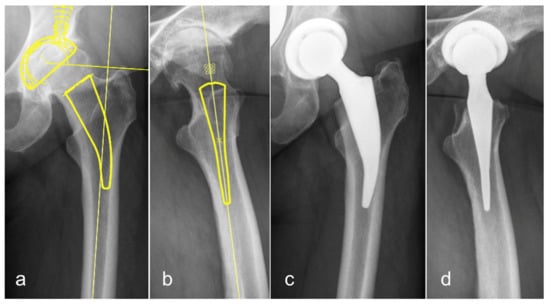

3.3. Short Stem Total Hip Arthroplasty (STHA)—Conventional Templating in One Plane on the a.p. Pelvic Overview

3.4. STHA—Templating in Two Planes—a.p. and Lateral View